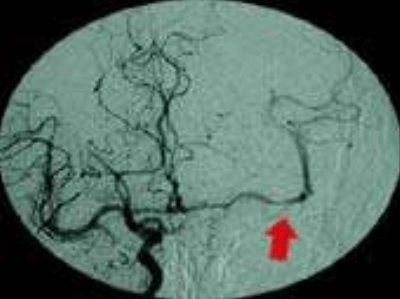

在 UCLA Health 医疗中心的介入神经放射学家和中风团队的护理下,南希接受了静脉注射 rTPA,以帮助身体分解血栓,同时将来自股动脉的一根小导管放置在腹股沟中,向上穿过阻塞的颈内动脉,并进入左侧大脑中动脉的血凝块,注入更多的 rTPA 分解血栓。该手术成功地重新打开了大部分南希的大脑中动脉,手术后当晚,她就恢复了说话的能力,并能重新移动身体右侧。